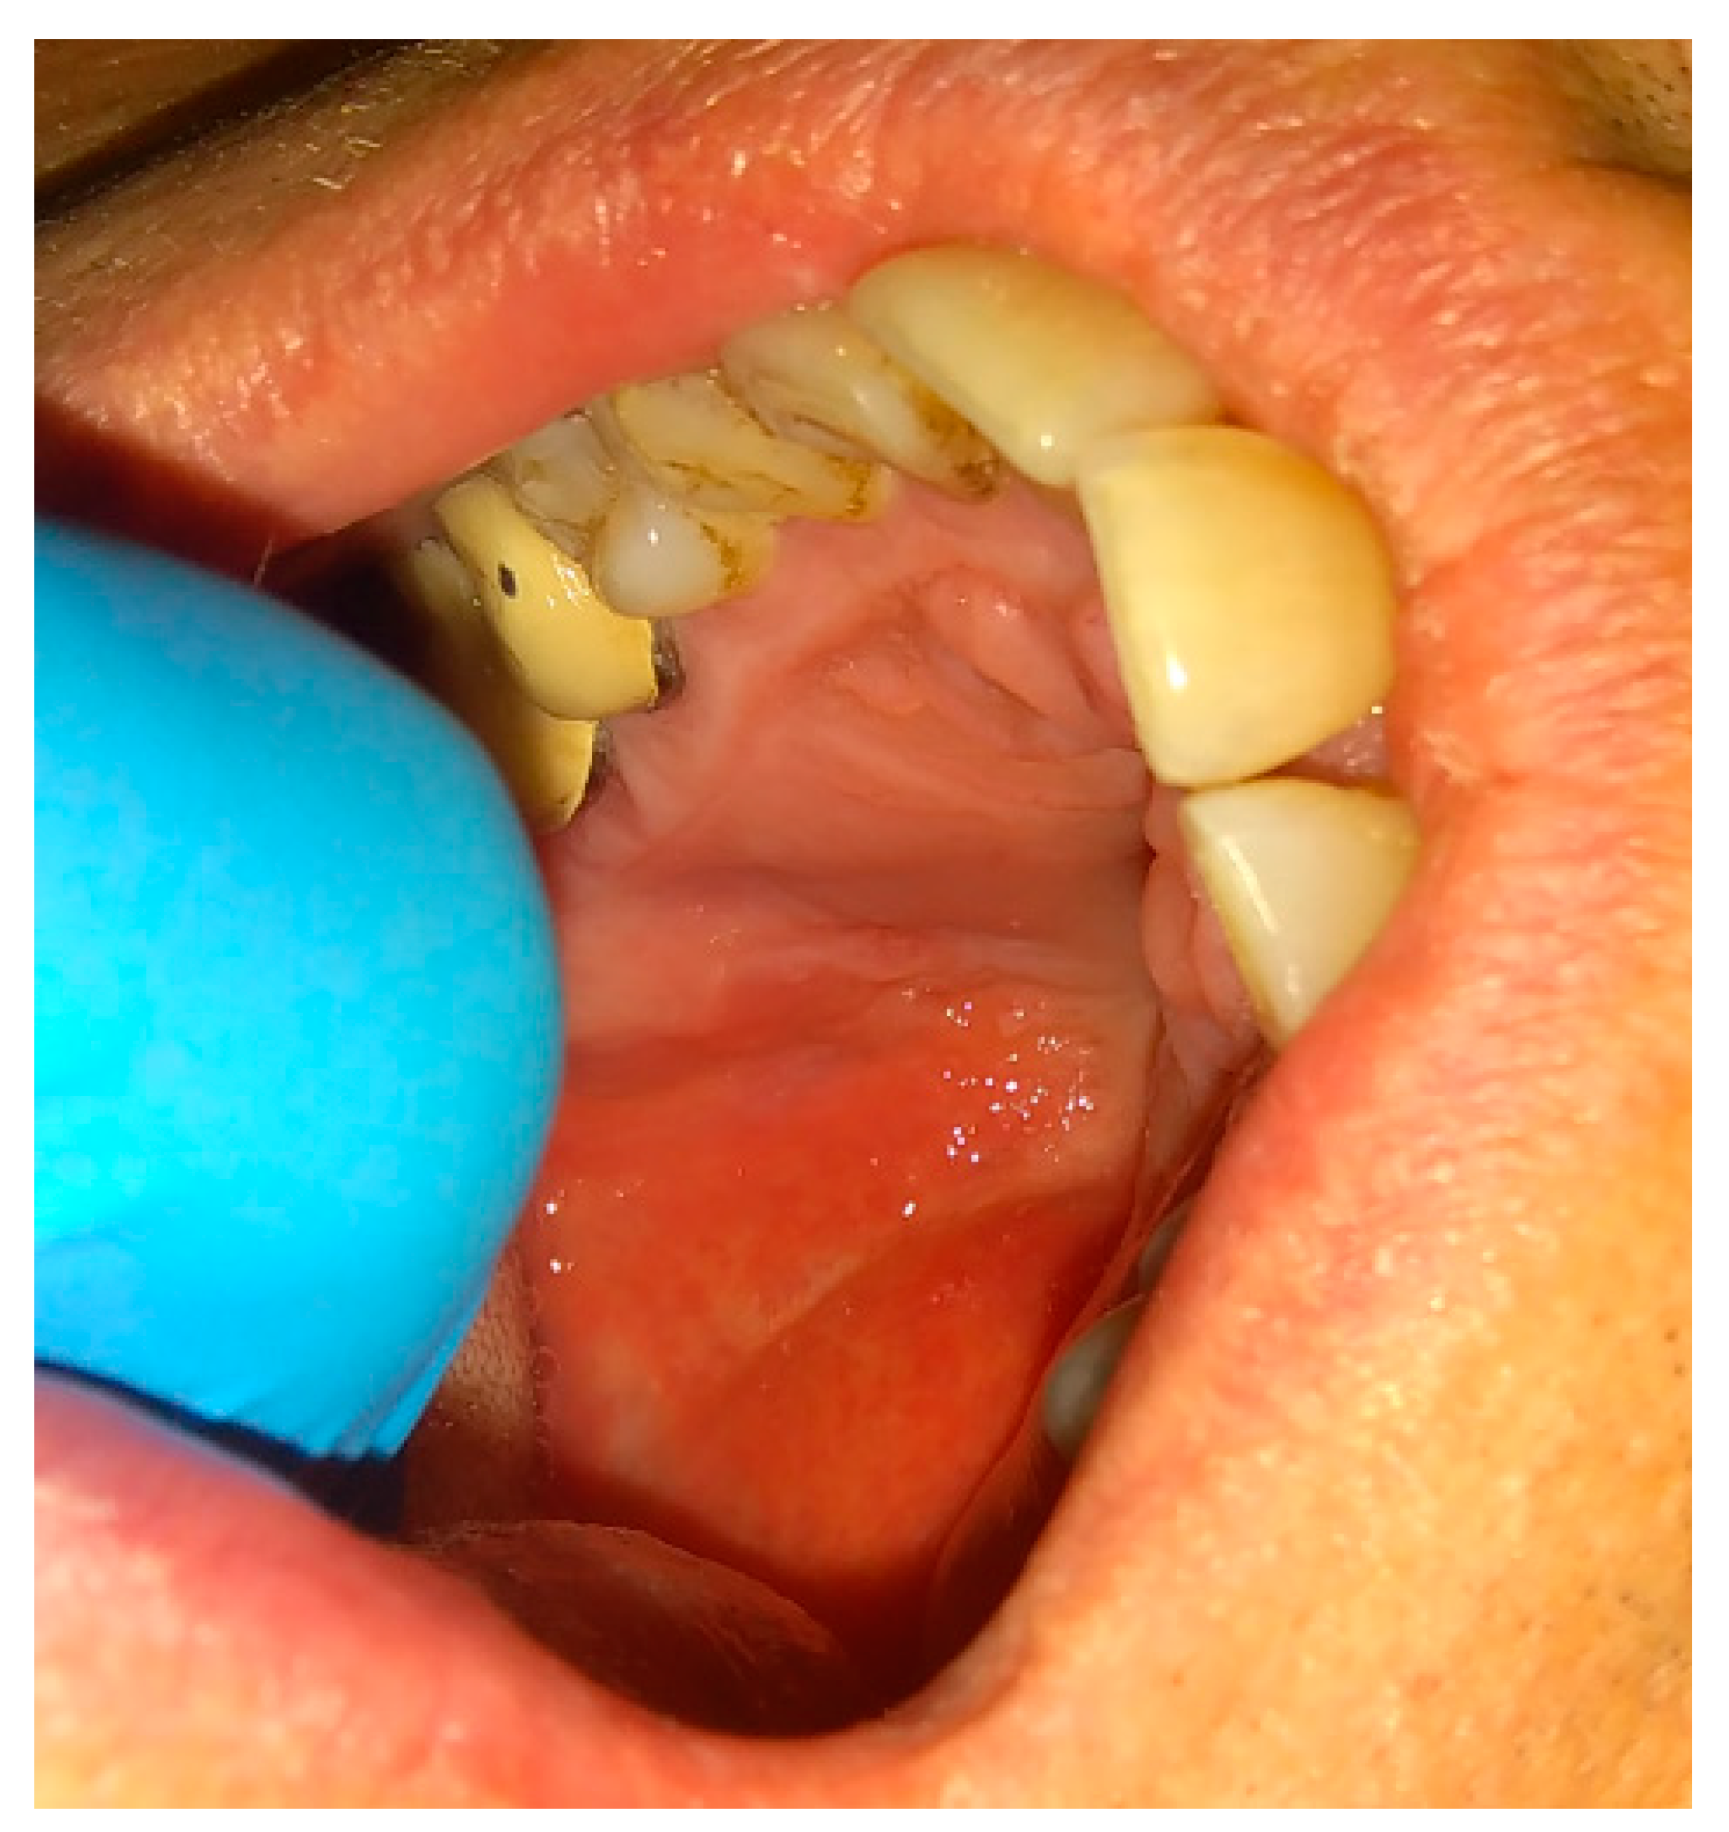

The rotation of the palatal flap can be used to solve some problems with the closure without buccal depth loss and esthetic function reduction. A full-thickness flap that contains the palatal artery is a good option to close an oro-antral communication. However, this procedure creates great morbidity and requires a long post-operative care period of the donor site on the palate. Flexibility possibilities of the palatal flap are limited, which forces the surgeon to create a large incision to assure the rotation of a sufficient amount of tissues. Second, the palatal defect heals via granulation, which is also troublesome for the patient. The location on the vestibular sulcus of the maxillary alveolar bone and the large size of the lesion support the choice of the pedicled buccal fat pad flap technique [21]. In some cases of bigger maxillary sinus wall deficiencies, the suturing can be troublesome, especially when it causes severe buccal narrowing or is sutured with tension. A free-of-tension suturing of any oroantral communication is easily achieved with the BFP and can be easily used for suturing in any dental surgery (Figure 1, Figure 2, Figure 3 and Figure 4).

Figure 4. A very good result with limited buccal corridor narrowing and good tissue volume at the top of the dental arch.